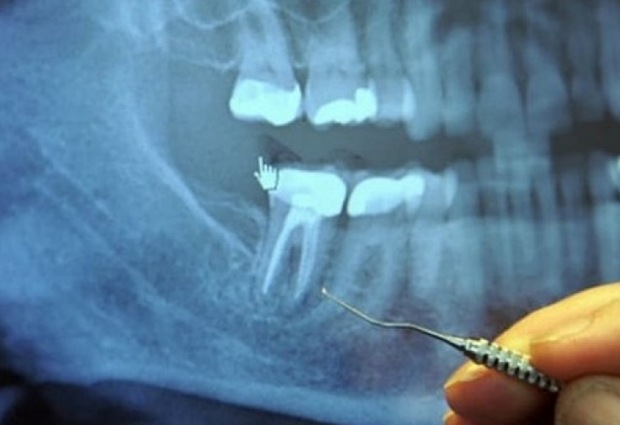

За коя стоматологична процудура става въпрос? Става въпрос за отстраняване на нерв. Милиони такива интервенции се извършват всяка година. Зъбите, които се екстрахират нерви са по същество „мъртви“ зъби, които могат да станат рай за силно токсични анаеробни бактерии .При определени условия може да навлязат в кръвта и да предизвикат редица сериозни заболявания. И това е интересно: Флуорът в пастата за зъби ни разболява.

Оказва се, че много хронични дегенеративни заболявания, произхождащи от заразени зъби без нерви, от които най-често сърдечни и заболявания на кръвообращението. Открива силна връзка между зъбите с извадени нерви и ставни заболявания, на мозъка и нервната система. Зъбите са изработени от най-силното вещество в нашето тяло. В средата на всеки зъб има зъбни кухини, които свързват кръвоносните съдове и нерви. Около зъбната кухина е дентина, който се състои от живи клетки, които секретират твърдо минерално вещество. Външната част на зъба, наречена емайл и дентина. Корените на всеки зъб остават по местата, благодарение на периодонтални връзки.

Зъболекарите в училище учат, че всеки зъб има по-голям канал 1-4. Въпреки това, има един куп канали, които не са споменати изобщо. Всеки зъб има цял лабиринт от малки тръбички, които ако се развият, ще имат дължина няколко километра. Уестън Прайс идентифицира 75 отделни канала за достъп в централен резец. Микроскопични организми редовно се движат в и около тези тръби като в „мол“ от подземни тунели. Когато зъболекар извършва операция по отстраняване на нерв, той запълва кухина, като прекъсва притока на кръв до зъба, така че тя вече не може да циркулира през зъба. Въпреки това, лабиринта от тръби остава там, и бактериите, които вече не са източник на храна, се крият в тези тунели, където те са на безопасно място от антибиотици и имунната защита на организма.